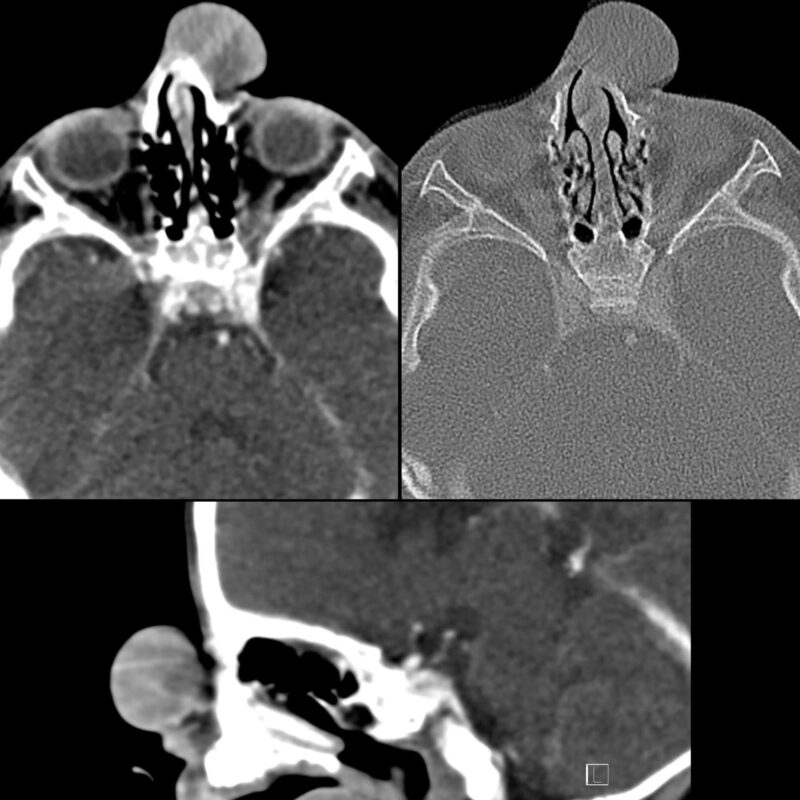

“Infant with a nasal mass.

Axial CT with contrast of the face in soft tissue (above left) and bone (above right) windows shows a nasal mass of soft tissue density arising off the dorsal aspect of the nose and splaying the nasal bones.

Sagittal CT (below) shows there is no evidence of intracranial extension.

The diagnosis was nasal glioma.